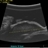

- ciliary body mass, immersion ultrasound, cystic lesion

- Ultrasonography device

- Immersion ultrasound of mass shows cystic lesion 11mm in diameter